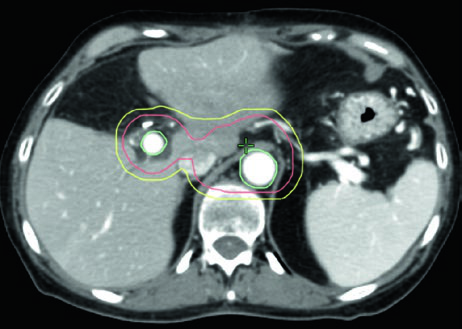

Volúmenes blanco en el escenario definitivo

| Volumen | Definición y descripción |

|---|---|

| GTV | Toda enfermedad macroscópica en imagen, incluyendo el tumor primario y la extensión vascular |

| ITV (opcional) | Si se utiliza enfoque ITV, delinear el GTV en todas las fases del 4D-CT |

| CTV alta dosis | Corresponde al GTV (o ITV si se utiliza) sin margen adicional |

| CTV dosis microscópica | Expansión uniforme ≥ 1 cm sobre toda la enfermedad macroscópica + cadenas CA y AMS + hilio esplénico (cuerpo/cola) + margen vascular adicional + porta hepatis opcional (cabeza) |

| PTV alta dosis | Expansión 0–0,5 cm, sustrayendo OARs críticos superpuestos con margen de seguridad: • 56 Gy/28 fx o 33 Gy/5 fx: sustraer estómago e intestino delgado sin margen adicional • 50 Gy/10 fx, 67,5 Gy/15 fx o 75 Gy/25 fx: sustraer con expansión de 0,5 cm (0,7 cm para interfaz larga) |

| PTV microscópico | Mínimo 0,5 cm; sin ITV en respiración libre, 1–1,5 cm craneocaudal |

Un detalle práctico que a menudo se subestima: dada la naturaleza infiltrativa del PDAC, el sobre-contorneo del GTV para incluir el parénquima pancreático circundante puede ser razonable, especialmente cuando se respalda con imagen diagnóstica adicional. En regiones de contacto directo entre GTV y OAR crítico, el PTV debe excluir el OAR con un margen de seguridad que exceda la expansión del PRV.